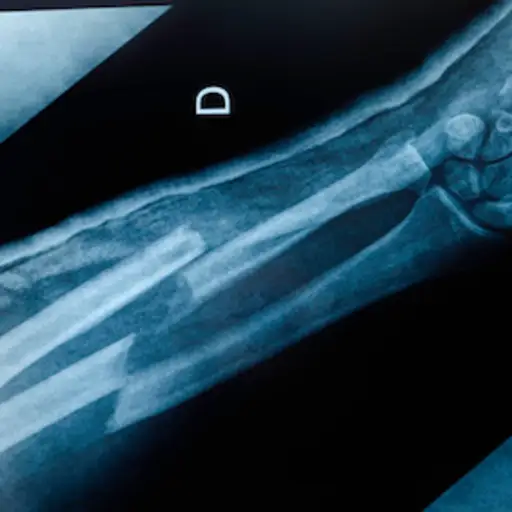

误解:每个患骨质疏松症的人都至少有一次骨折

事实:三分之一的女性和五分之一的男性患有骨质疏松性骨折国际骨质疏松症基金会.你的医生可以和你一起确定你的骨折风险你可以采取什么措施来降低这种风险。